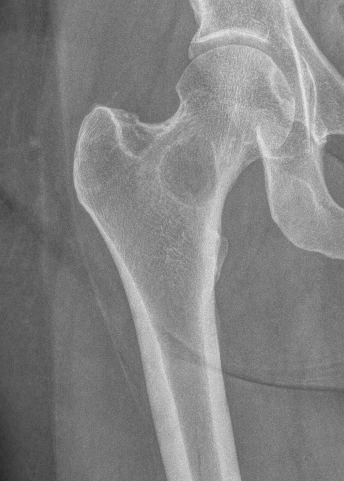

Femoral Neck pathological fracture / Major bone loss

Issues

- fracture unlikely to heal

- hemi versus THA

- long versus short stems